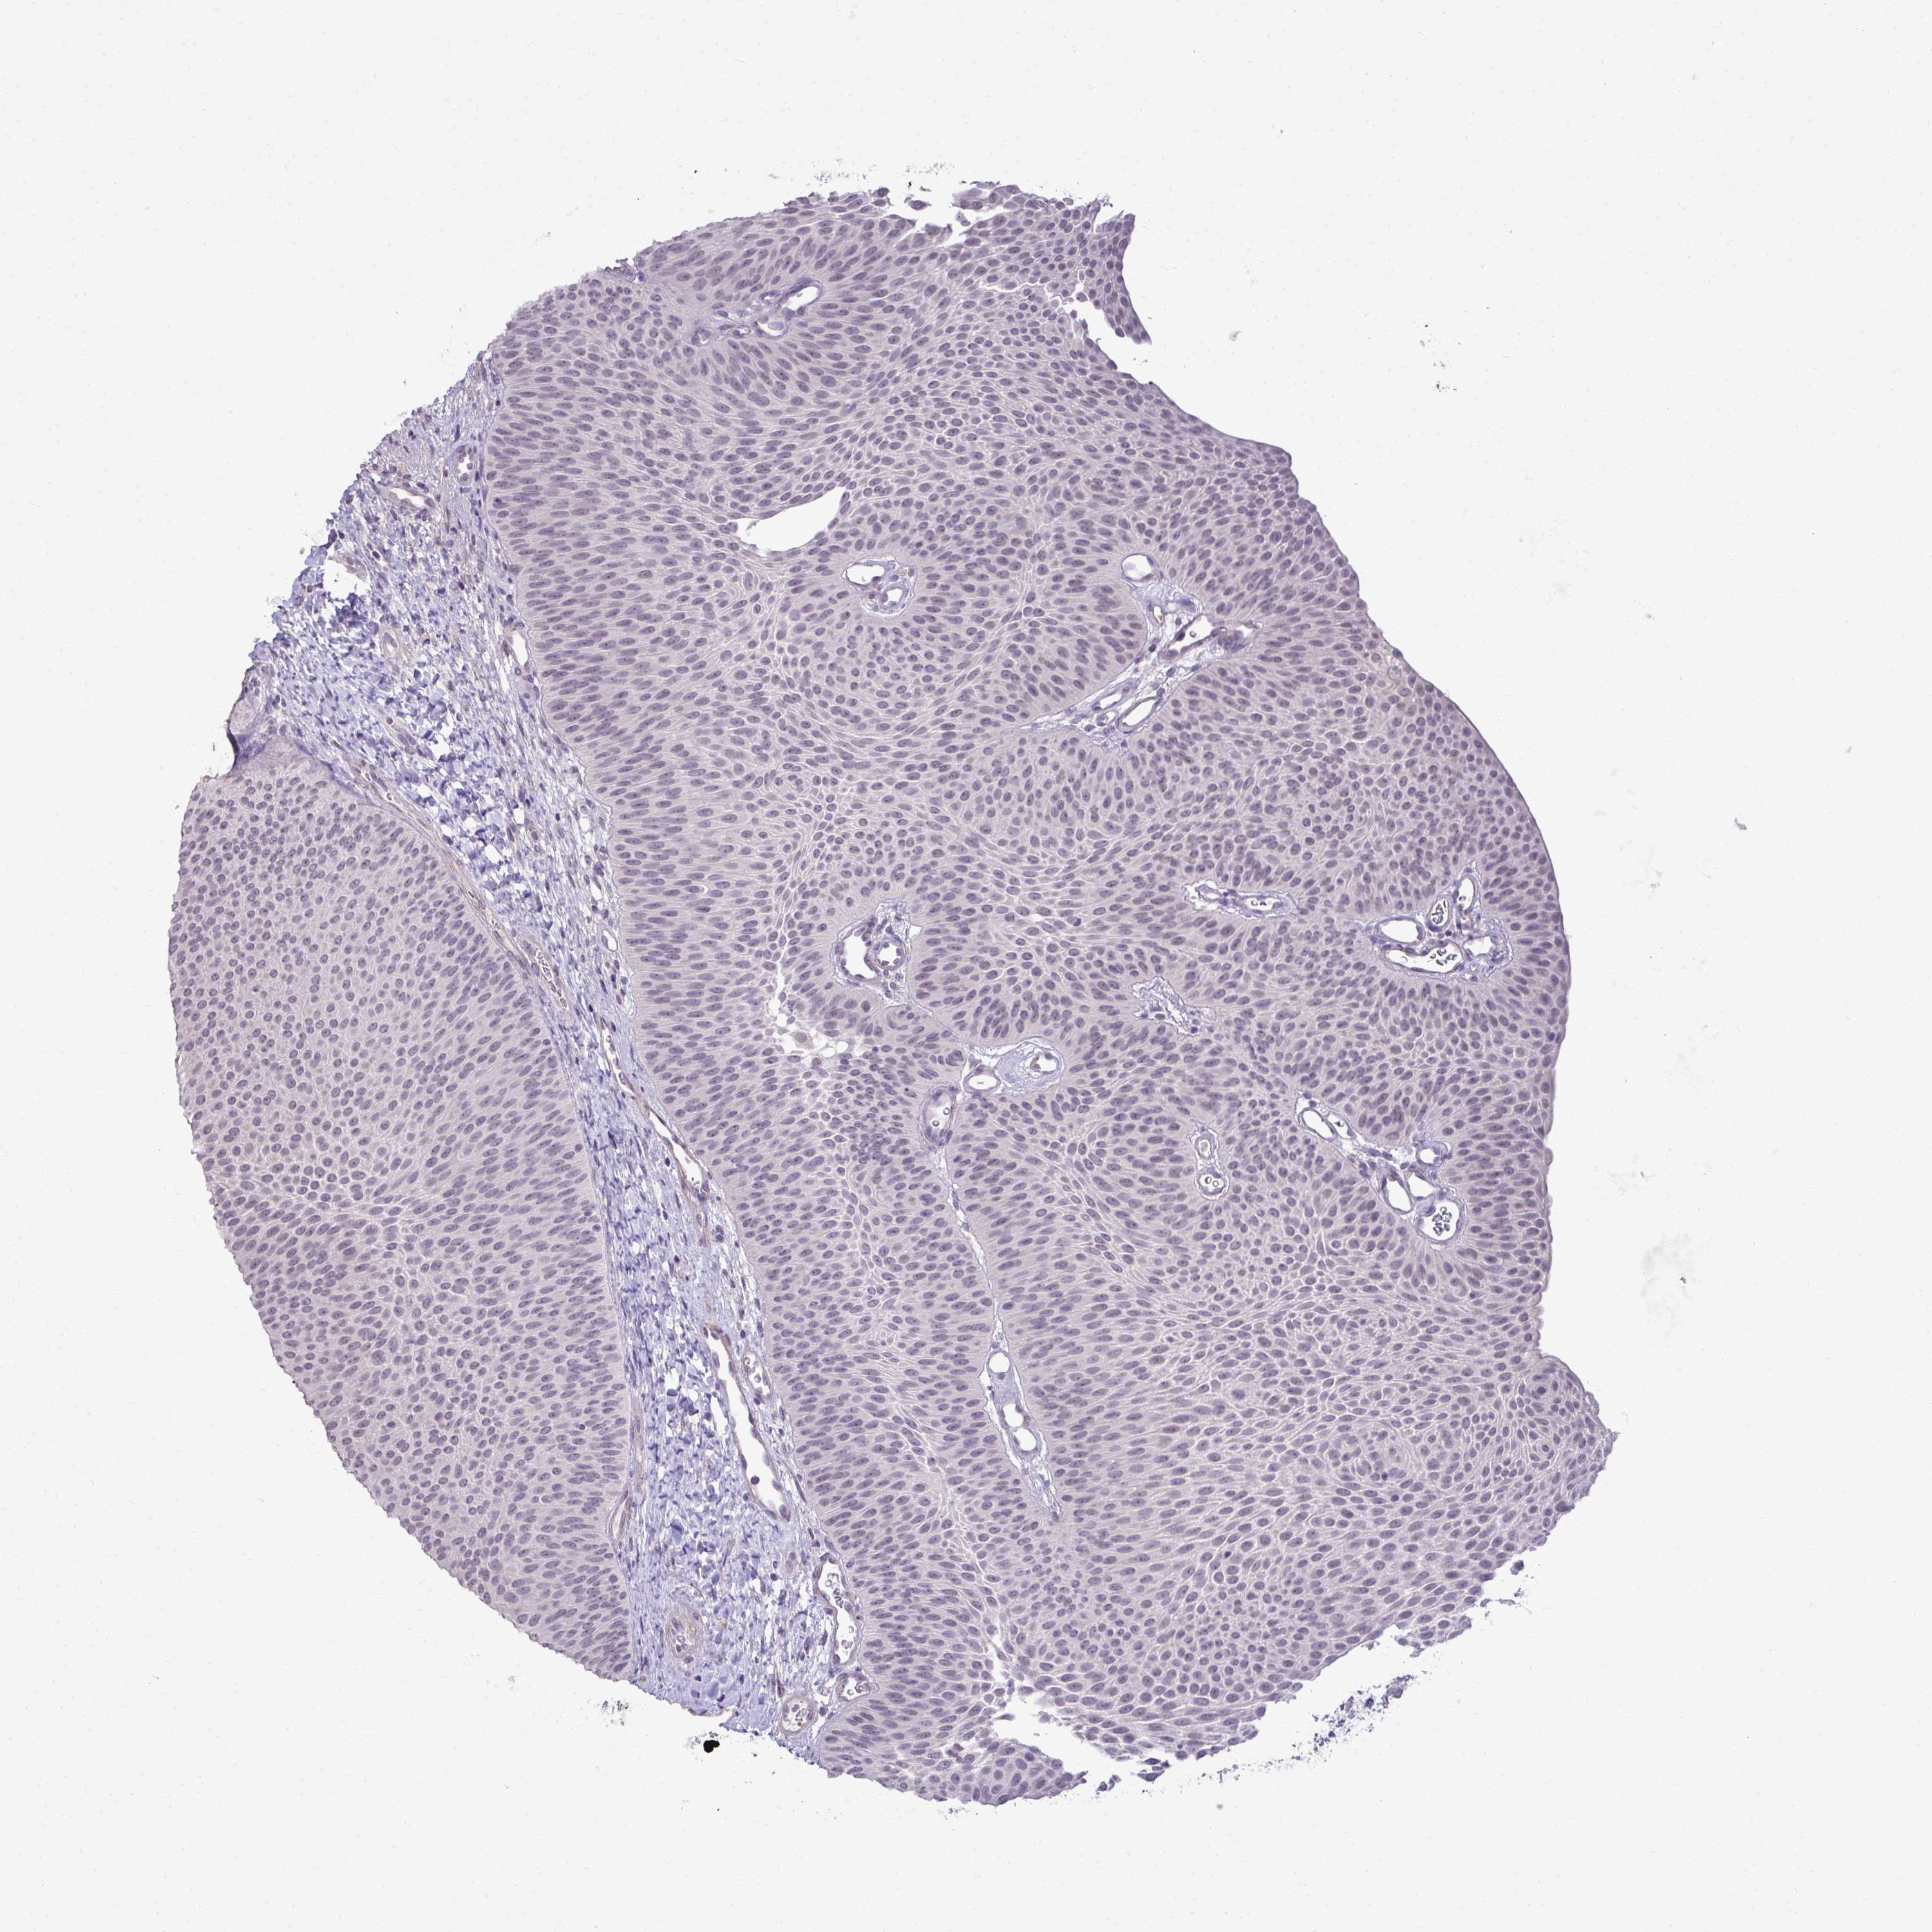

UROTHELIAL CANCER - Protein expressioni

A mouse-over function shows sample information and annotation data. Click on an image to view it in a full screen mode. Samples can be filtered based on level of antibody staining by selecting one or several of the following categories: high, medium, low and not detected. The assay and annotation is described here.

Antibody stainingi

Antibody staining in the annotated cell types in the current human tissue is reported as not detected, low, medium, or high, based on conventional immunohistochemistry profiling in selected tissues. This score is based on the combination of the staining intensity and fraction of stained cells.

Each image is clickable and will lead to virtual microscopy that enables deeper exploration of all samples and also displays staining intensity scores, fraction scores and subcellular localization as well as patient and tissue information for each sample.

Antibody HPA060505

Antibody HPA067637

Urothelial carcinoma, High grade

Urothelial carcinoma, Low grade

Urothelial carcinoma, NOS